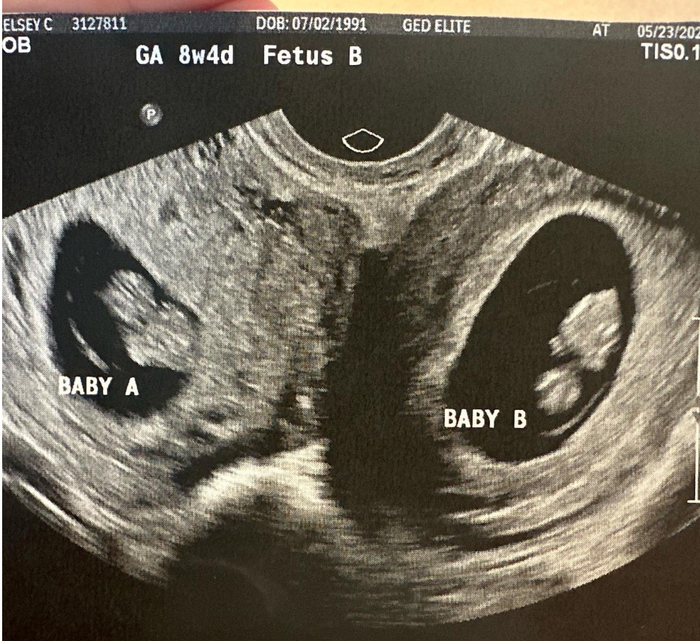

B超检查显示,凯尔西·哈彻的两个子宫同时妊娠。图源/IG

今年5月,凯尔西怀孕八周,做了第一次产检。B超医生看到胎儿一切正常、很健康。凯尔西提醒医生再照照另一边,因为她有着异于常人的生理结构。

B超医生把超声波头移到腹部另一侧。不一会儿,医生惊呼:“天哪,这里还有一个。”